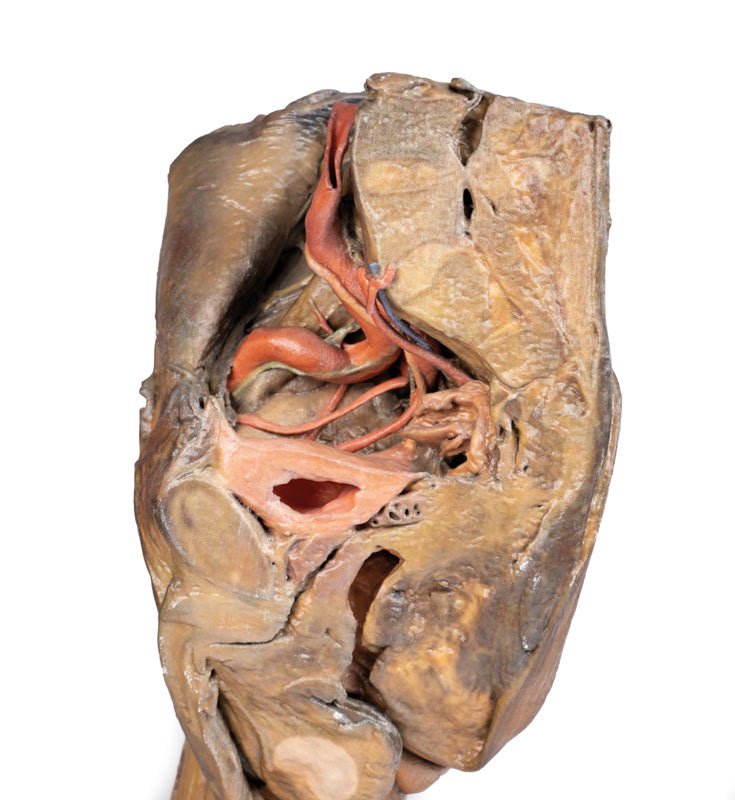

3D dissektionsmodellerne kan opbevares hvor som helst og uden brug af formalin. En sundshedssikker fremstilling og opbevaring gør disse modeller tilgængelige for alle inklusiv eksempelvis gravide studerende, som normalt må undvære undervisningen med præparater grundet formalinen skadelige virkninger.

Fremstillet med den nyeste 3D printteknologi og 100% syntetiske materialer, er 3D disssektionsmodellerne en tro kopi af den ægte vare, men uden smitterisikoen der normalt følger med ægte præparater.

Vores 3D dissektionsmodeller er udviklet med tilladelse til anvendelse af alle. I modsætning til kadavere, der stiller krav til anvendelsen og enorme ressourser i tilblivelsen af blot et enkelt præparat, både kemisk og i arbejdskraft, kan vores modeller produceres forvarligt, anvendes af flere og opbevares hvor som helst